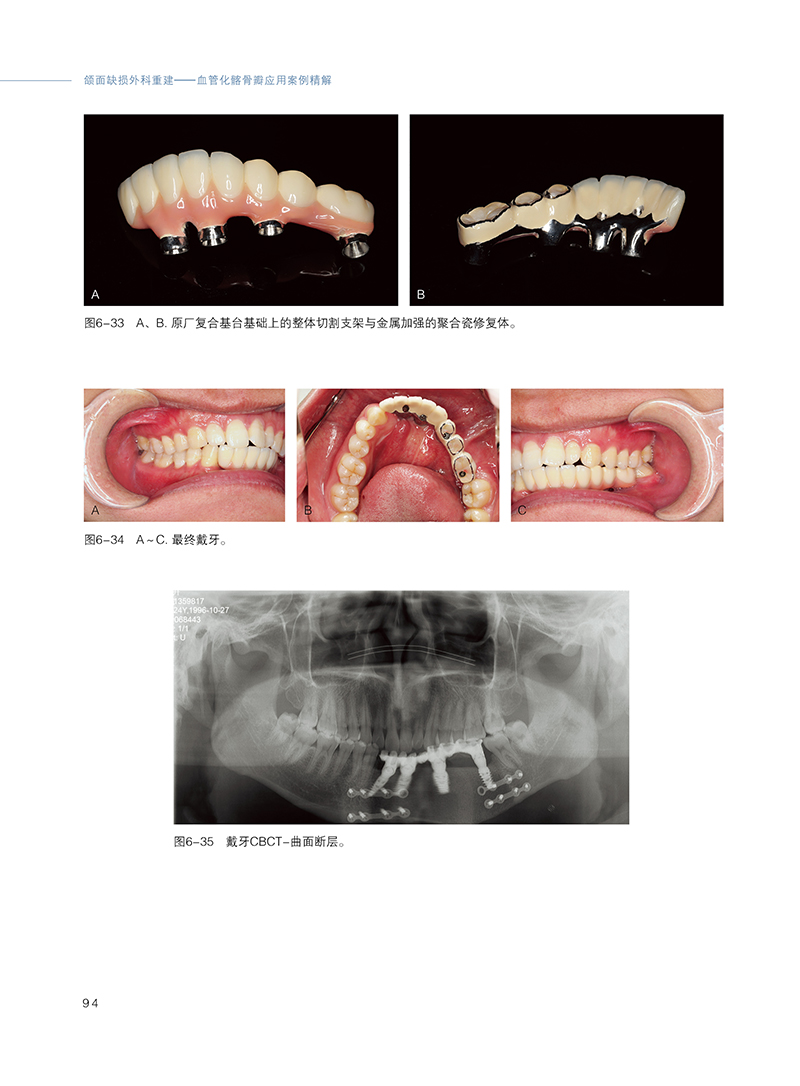

《颌面缺损外科重建——血管化髂骨瓣应用案例精解》